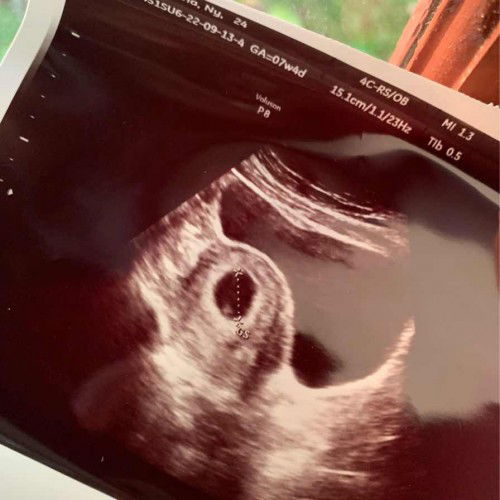

Usia Kandungan 7weeks masih kantung saja?

Sore bunda bunda. Mau sharing sedikit. Jadi aku hamil anak prtama, dgn usia kandungan 7weeks(hpht). Di usia 5week aku udah USG untk mastiin beneran hamil atau tidak, saat USG trnyta baru kliatan kantungnya kecil bangettttttt. Jdi untuk memastikan bahwa beneran hamil atau engga, dokter menyarankan untk datang lg 2minggu kmudian. Stlh 2minggu tepat hari ini, aku USG lg. Hasil USG nya kaya gitu. Klo kata dokternya janinnya blum keliatan bru pnebalan kantung nya aja. Coba 1bulan lg kontrol lagi, klo gada perubahan trpaksa harus dikluarkan, sumpah demi apapun aku shock bgt, berasa tertampar, aku jdi brtanya2, apakah berkembang atau tidak. Tpi aku lihat itu ada titik kecil didalam kantungnya, apakah itu janinnya bunda? Aku jdi semakin OVT. Sumpah😢 tp ttp berusaha mikir positif. Ada yg sama ga ya bund usia 7weeks tp baru keliatan kaya gitu?